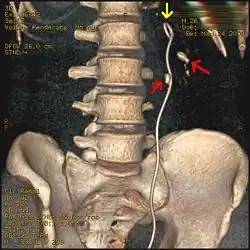

Calcium-containing stones are relatively radiodense (opaque to X-rays), and they can often be detected by a traditional radiography of the abdomen that includes the kidneys, ureters, and bladder (KUB film).[59] KUB radiography, although useful in monitoring size of stone or passage of stone in stone formers, might not be useful in the acute setting due to low sensitivity.[60] Some 60% of all renal stones are radiopaque.[61][62] In general, calcium phosphate stones have the greatest density, followed by calcium oxalate and magnesium ammonium phosphate stones. Cystine calculi are only faintly radiodense, while uric acid stones are usually entirely radiolucent.[63]

Otherwise a noncontrast helical CT scan with 5 millimeters (0.2 in) sections is the diagnostic method to use to detect kidney stones and confirm the diagnosis of kidney stone disease.[16][57][61][66][7] Near all stones are detectable on CT scans with the exception of those composed of certain drug residues in the urine,[59] such as from indinavir.

Where a CT scan is unavailable, an intravenous pyelogram may be performed to help confirm the diagnosis of urolithiasis. This involves intravenous injection of a contrast agent followed by a KUB film. Uroliths present in the kidneys, ureters, or bladder may be better defined by the use of this contrast agent. Stones can also be detected by a retrograde pyelogram, where a similar contrast agent is injected directly into the distal ostium of the ureter (where the ureter terminates as it enters the bladder).[61]

Renal ultrasonography can sometimes be useful, because it gives details about the presence of hydronephrosis, suggesting that the stone is blocking the outflow of urine.[59] Radiolucent stones, which do not appear on KUB, may show up on ultrasound imaging studies. Other advantages of renal ultrasonography include its low cost and absence of radiation exposure. Ultrasound imaging is useful for detecting stones in situations where X-rays or CT scans are discouraged, such as in children or pregnant women.[67] Despite these advantages, renal ultrasonography in 2009 was not considered a substitute for noncontrast helical CT scan in the initial diagnostic evaluation of urolithiasis.[66] The main reason for this is that, compared with CT, renal ultrasonography more often fails to detect small stones (especially ureteral stones) and other serious disorders that could be causing the symptoms.[14]